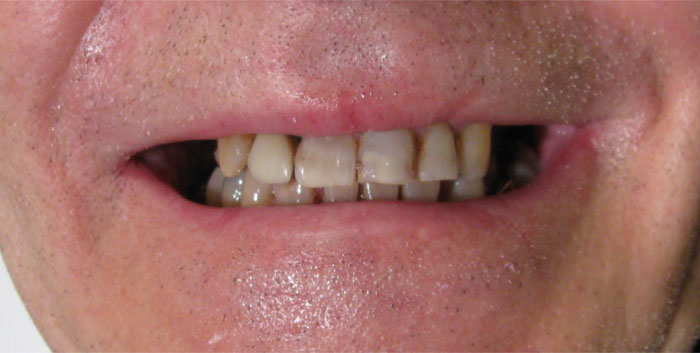

CAS N°1 Bridges et couronnes sur implant dentaire DIO et sur dents naturelles. Réhabilitation complète mâchoire supérieure, détartrage et blanchiment mâchoire inférieure.

Europa Dental Hongrie